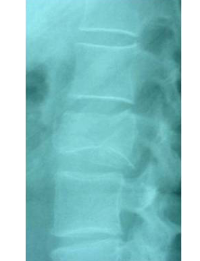

Pre- and post-operative comparison of a cemented kyphoplasty

Female, age 55, compression fracture of L2

Before 1

Before 2